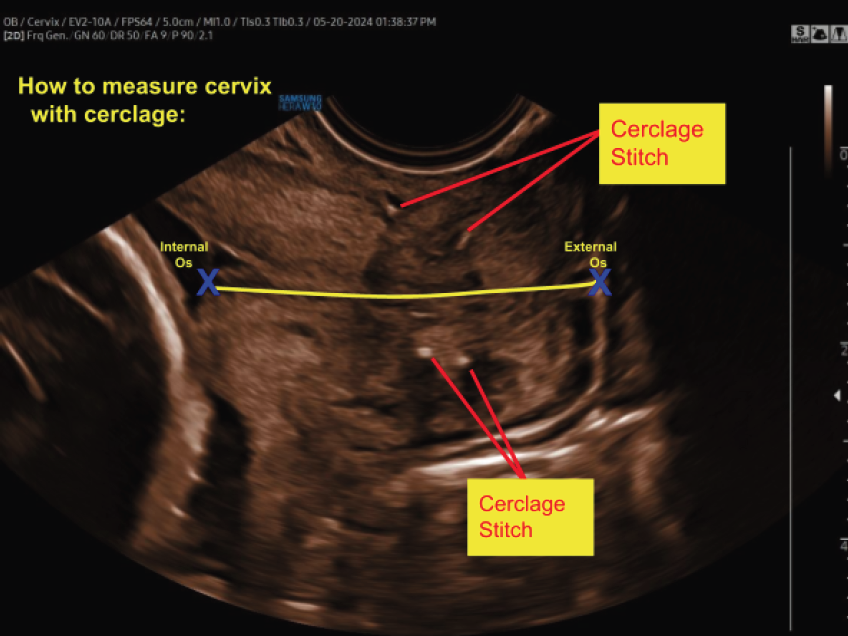

McDonald Cerclage: The McDonald cerclage is the most common procedure. It involves placing a stitch around the cervix, essentially creating a supportive loop that holds the cervix closed.

An ultrasound-indicated cerclage is a wise choice when a woman’s cervical length measures less than 24 mm, particularly if she has a history of spontaneous preterm births or mid-trimester losses. Significantly, for those expecting twins, the threshold for intervention is even shorter, with cervical lengths under 15 mm suggesting the need for this supportive measure.

Regular cervical length monitoring is another vital aspect of managing this condition, ensuring any changes are promptly detected. It's crucial to have an in-depth discussion with healthcare providers about these treatments, enabling patients to make the most informed and personalized decisions for their health and their baby's well-being.

Why It Matters to Sonographers